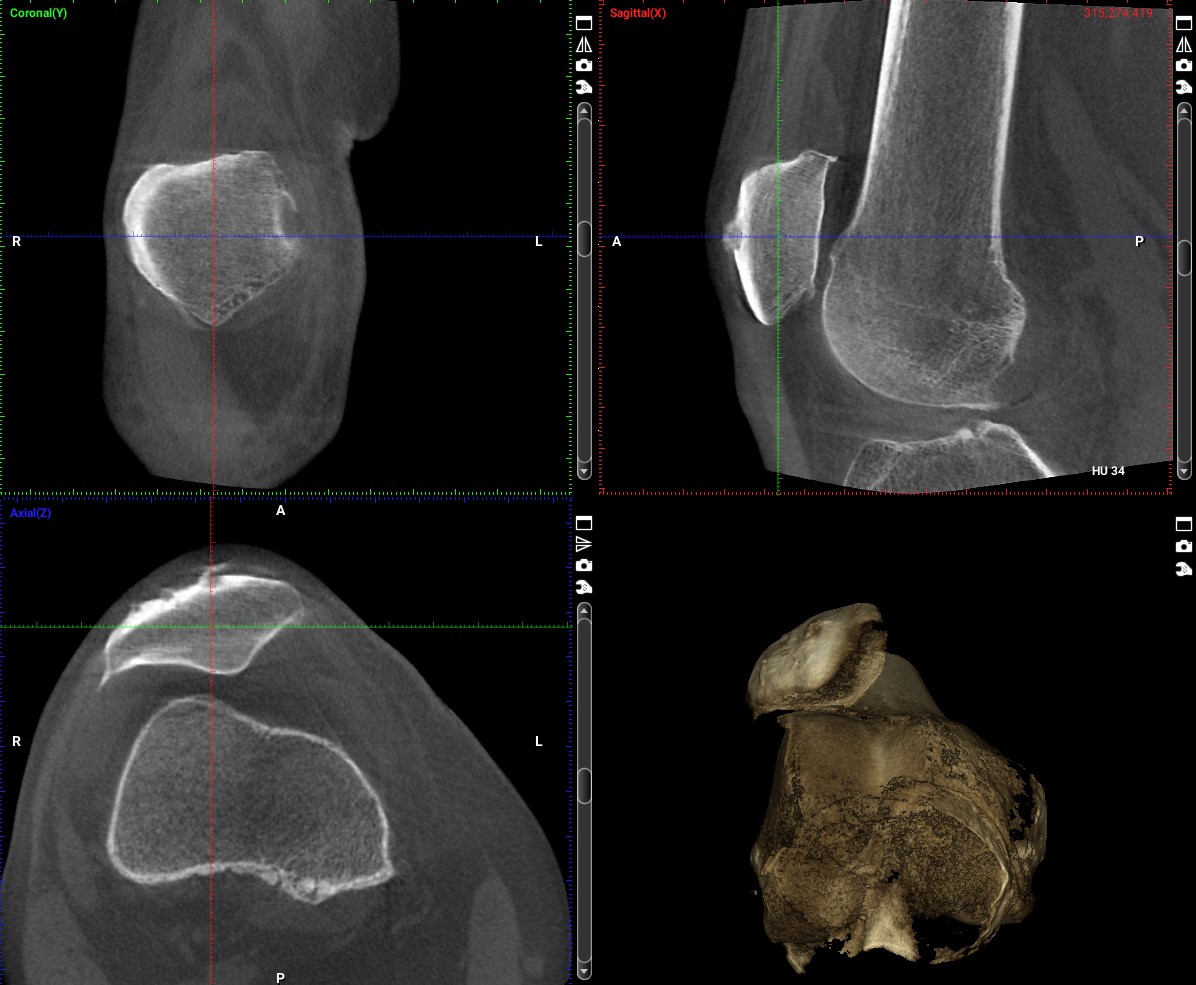

- Genaue Lokalisation freier Gelenkkörper,

- Erkennung der Früharthritis durch exakte Darstellung der Gelenkflächen,